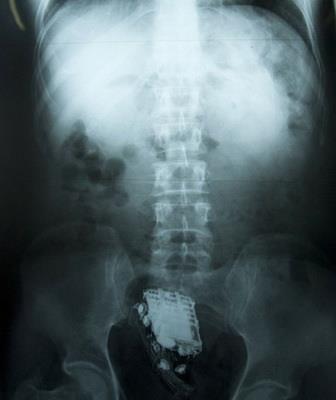

Jedan zatvorenik u državi Šri Lanka sakrio je mobilni u svoj anus u pokušaju da ga sakrije prilikom iznenadnog pretresa ćelija.

Na njegovu žalost uređaj je na kraju ipak otkriven tako što su čuvari zatvora u jednom trenutku čuli zvonjavu telefona i shvatili da dolazi iz njegove zadnjice.

Osuđenik je morao da bude odveden u bolnicu kako bi mu izvadili telefon.

"Muškarac je u u sebe sakrio mobilni. Na njegovu žalost on je zazvonio u najgorem mogućem trenutku i čuvari su shvatili odakle zvuk dolazi", izjavio je službenik zatvora.

Zatvorenik je u bolnici proveo dva dana i vraćen je u zatvorsku jedinicu u petak, a služi kaznu od 10 godina zbog teške krađe.